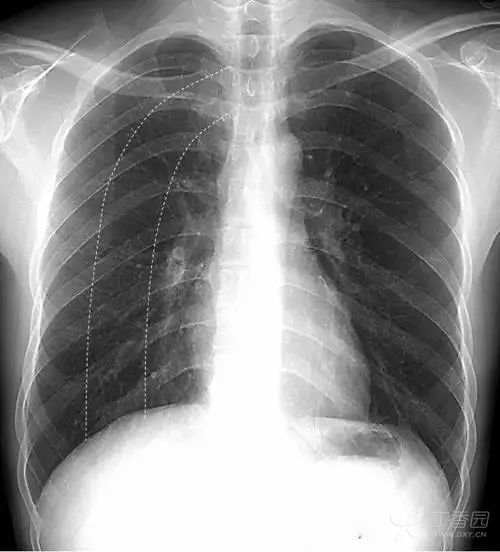

上图女性乳腺影重叠在两肺下野,导致两肺下野对称性密度增高,乳腺形成投影的下缘(白色箭头)是清晰锐利的并且呈半圆形,常向外与腋部皮肤连续。没有乳腺重叠的两肺肋膈角区域更透亮。

鉴别:①两侧乳腺常规比较对称,所以在正位胸片上,乳腺重叠导致的两肺下野的密度增高也是比较对称的。而两肺下野均有病变且有分布比较对称的病理情况是比较少见的。②乳腺影的下缘清晰锐利且呈半圆形,向外与腋部皮肤连续。而肺内的病变不会延续到两肺以外。